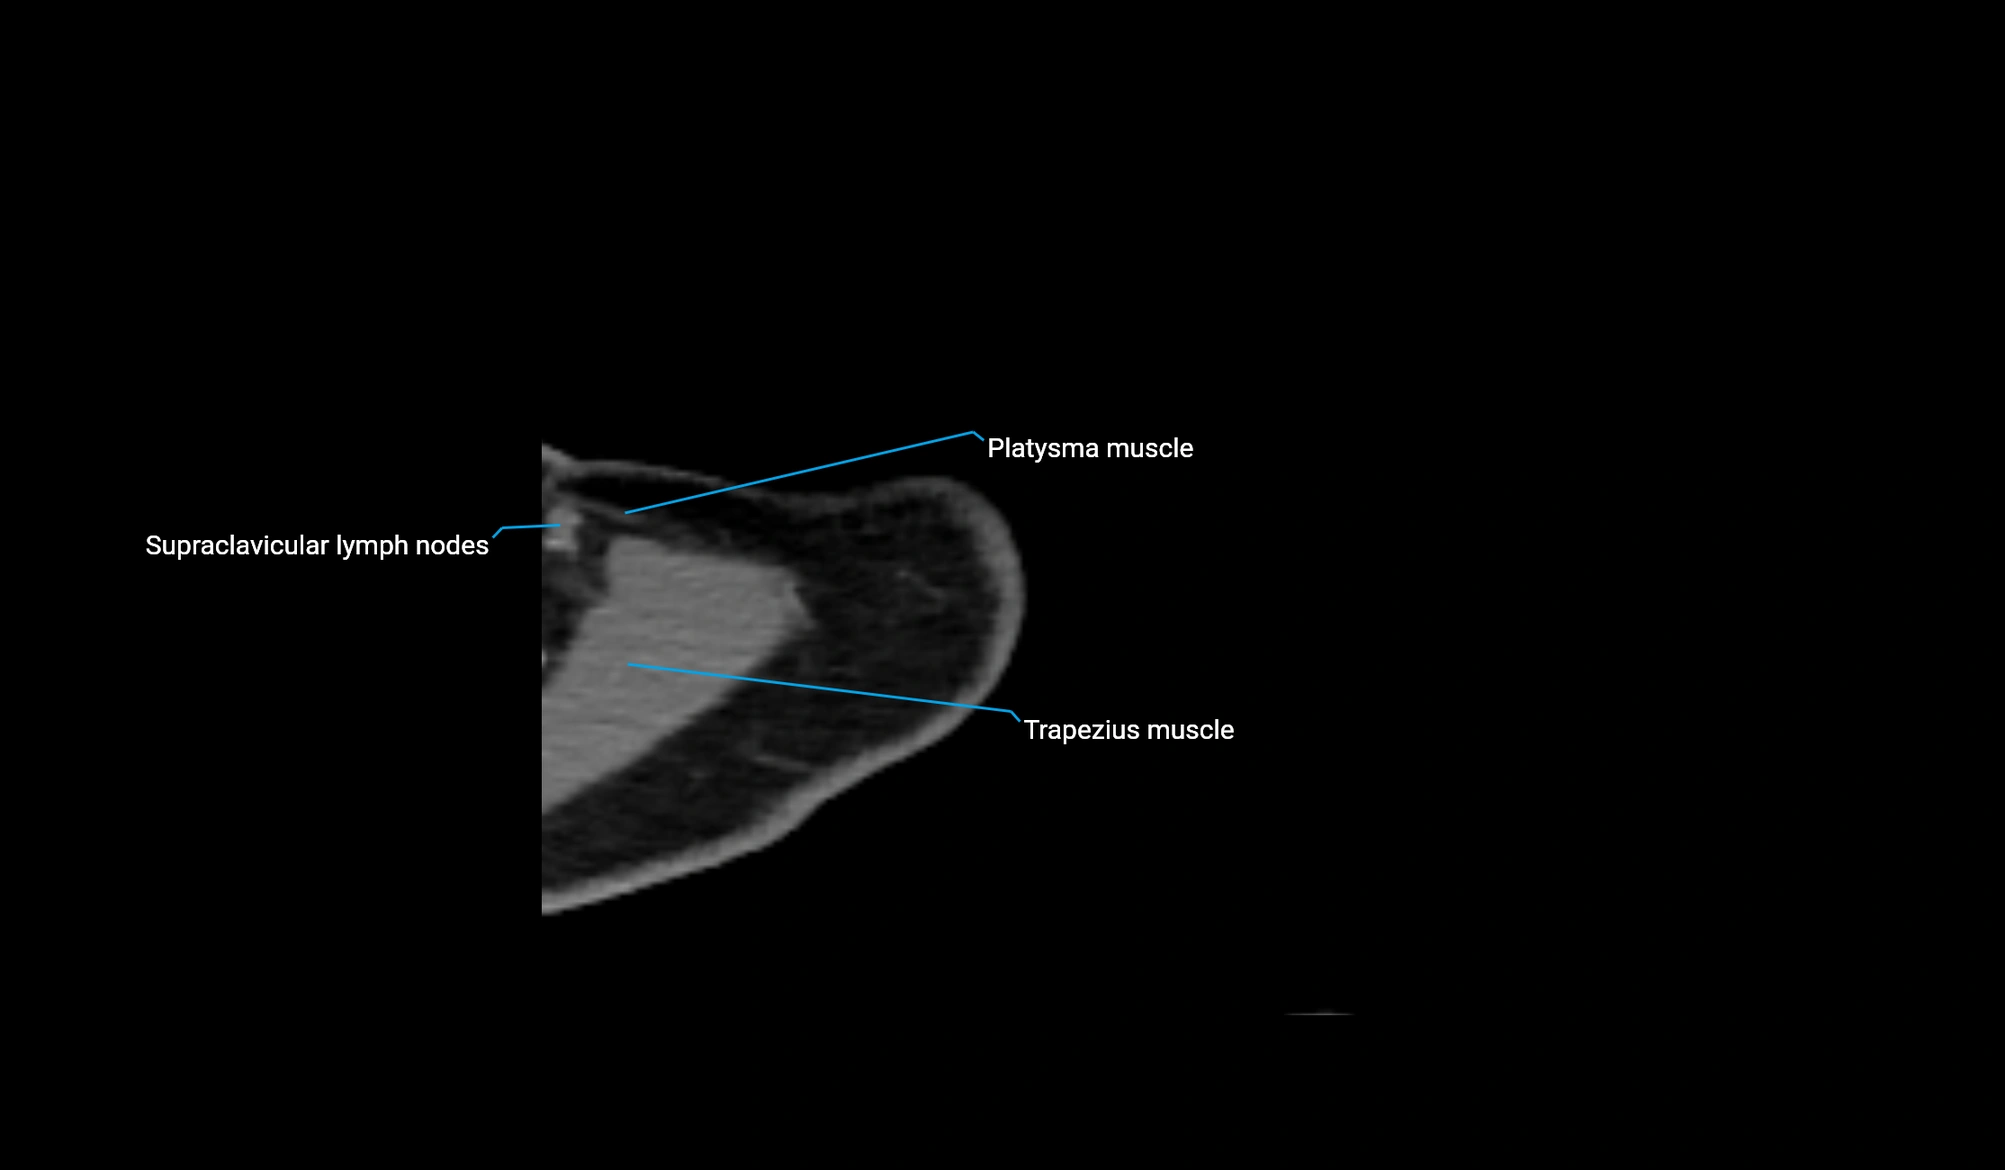

MRI image

CT image